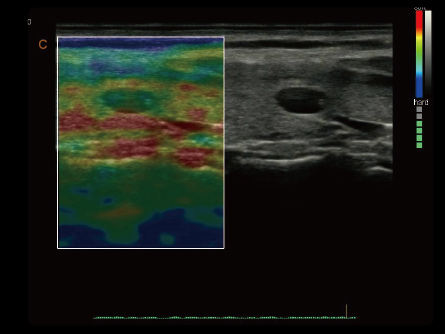

Potencie su práctica en Atención Primaria con las máquinas de ultrasonido de CHISON diseñadas para versatilidad y precisión. Nuestros productos están adaptados para abordar una amplia gama de necesidades de diagnóstico, ofreciendo interfaces fáciles de usar para exámenes eficientes. Las soluciones de ultrasonido de Atención Primaria de CHISON proporcionan imágenes claras y controles intuitivos, respaldando a los médicos generales en la realización de diagnósticos precisos y en la atención integral de los pacientes.